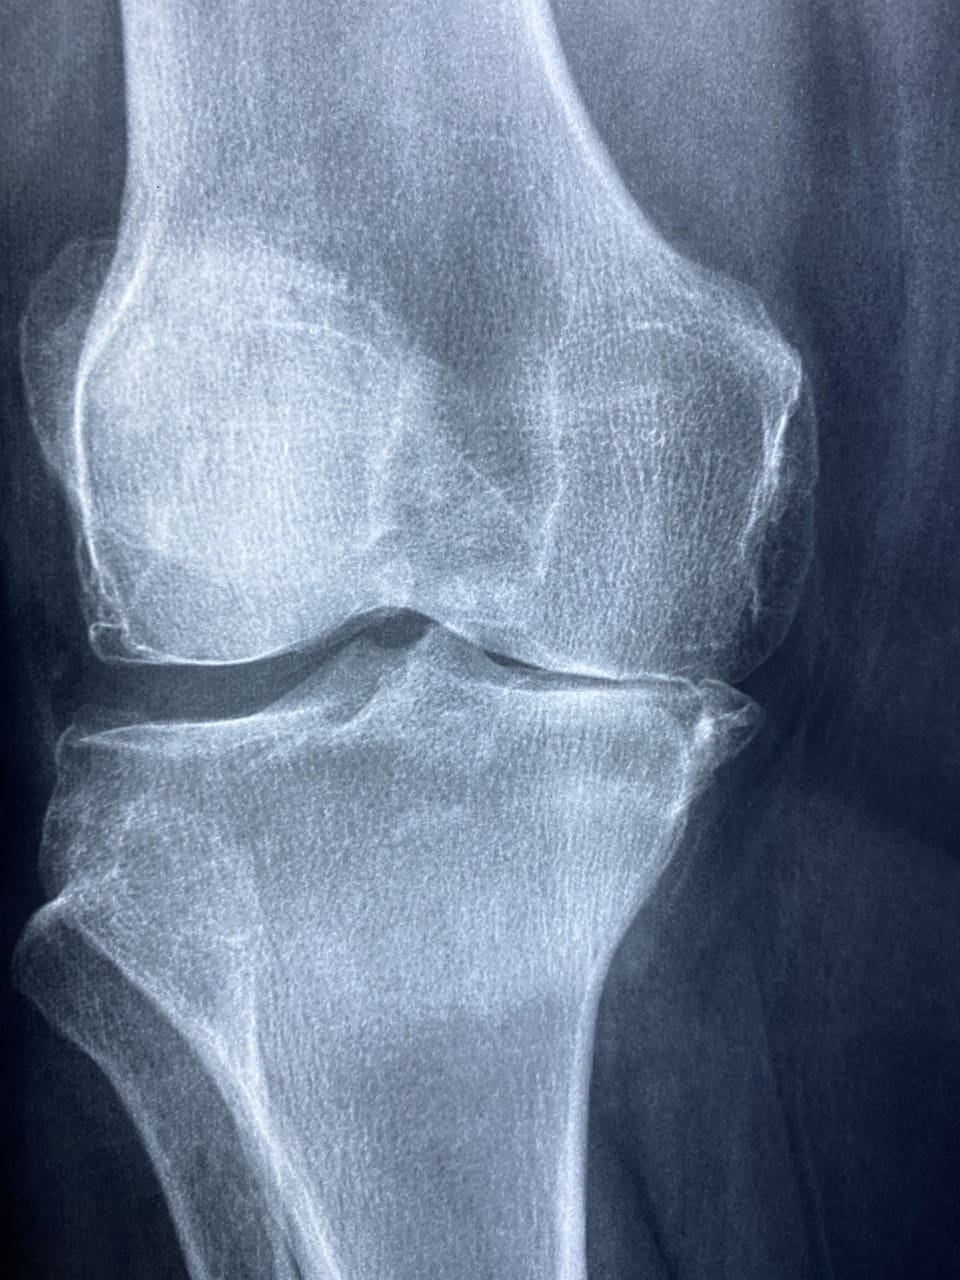

Living with rheumatoid arthritis means dealing with chronic inflammation, pain, and stiffness in the joints. This autoimmune disorder primarily affects the small joints in the hands and feet but can also impact other joints throughout the body. Staying physically active is essential for managing symptoms and preventing further joint damage. However, it’s important to choose exercises that are gentle on the joints and won’t exacerbate pain or inflammation.